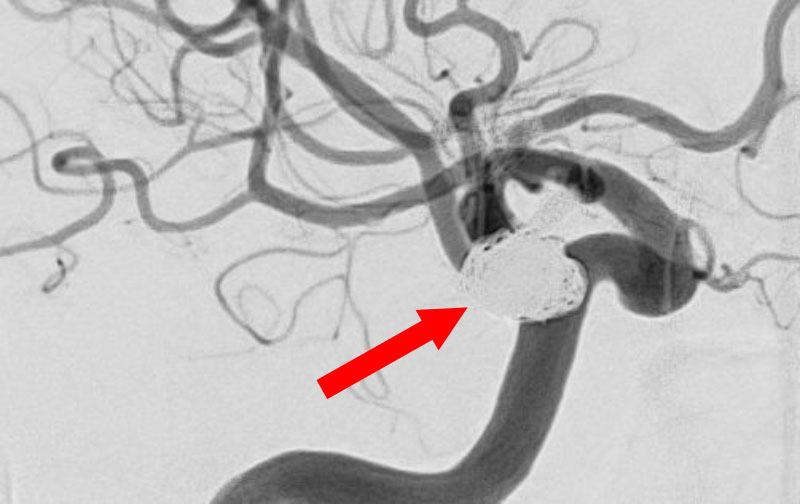

No.1602 手術前